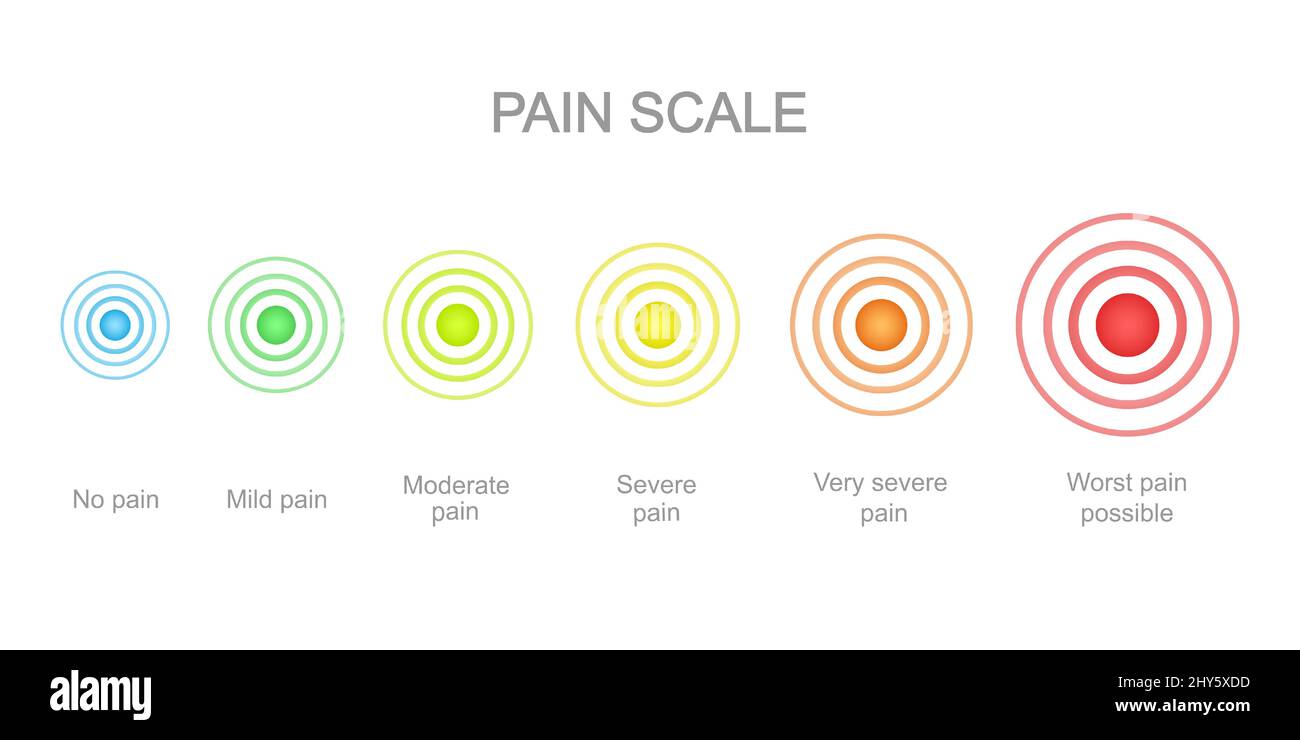

Schmerzmessskala mit mehrfarbigen Schmerzpunkten. Verletzte Messwertstände mit konzentrischen Anzeichen für die Lokalisierung von Schmerzen. Medizinisches Kommunikationstool für das Screening von Patientenerkrankungen. Vektorgrafik Stock Vektorhttps://www.alamy.de/image-license-details/?v=1https://www.alamy.de/schmerzmessskala-mit-mehrfarbigen-schmerzpunkten-verletzte-messwertstande-mit-konzentrischen-anzeichen-fur-die-lokalisierung-von-schmerzen-medizinisches-kommunikationstool-fur-das-screening-von-patientenerkrankungen-vektorgrafik-image464195801.html

Schmerzmessskala mit mehrfarbigen Schmerzpunkten. Verletzte Messwertstände mit konzentrischen Anzeichen für die Lokalisierung von Schmerzen. Medizinisches Kommunikationstool für das Screening von Patientenerkrankungen. Vektorgrafik Stock Vektorhttps://www.alamy.de/image-license-details/?v=1https://www.alamy.de/schmerzmessskala-mit-mehrfarbigen-schmerzpunkten-verletzte-messwertstande-mit-konzentrischen-anzeichen-fur-die-lokalisierung-von-schmerzen-medizinisches-kommunikationstool-fur-das-screening-von-patientenerkrankungen-vektorgrafik-image464195801.htmlRF2HY5XDD–Schmerzmessskala mit mehrfarbigen Schmerzpunkten. Verletzte Messwertstände mit konzentrischen Anzeichen für die Lokalisierung von Schmerzen. Medizinisches Kommunikationstool für das Screening von Patientenerkrankungen. Vektorgrafik

Schmerzskala mit konzentrischen Schmerzpunkten von blau bis rot. Verletzte Meterwerte mit mehrfarbigen Lokalisierungszeichen der Schmerzen. Medizinisches Tool für das Screening von Patientenerkrankungen. Vektorgrafik Cartoon-Illustration Stock Vektorhttps://www.alamy.de/image-license-details/?v=1https://www.alamy.de/schmerzskala-mit-konzentrischen-schmerzpunkten-von-blau-bis-rot-verletzte-meterwerte-mit-mehrfarbigen-lokalisierungszeichen-der-schmerzen-medizinisches-tool-fur-das-screening-von-patientenerkrankungen-vektorgrafik-cartoon-illustration-image467129079.html

Schmerzskala mit konzentrischen Schmerzpunkten von blau bis rot. Verletzte Meterwerte mit mehrfarbigen Lokalisierungszeichen der Schmerzen. Medizinisches Tool für das Screening von Patientenerkrankungen. Vektorgrafik Cartoon-Illustration Stock Vektorhttps://www.alamy.de/image-license-details/?v=1https://www.alamy.de/schmerzskala-mit-konzentrischen-schmerzpunkten-von-blau-bis-rot-verletzte-meterwerte-mit-mehrfarbigen-lokalisierungszeichen-der-schmerzen-medizinisches-tool-fur-das-screening-von-patientenerkrankungen-vektorgrafik-cartoon-illustration-image467129079.htmlRF2J3YFWB–Schmerzskala mit konzentrischen Schmerzpunkten von blau bis rot. Verletzte Meterwerte mit mehrfarbigen Lokalisierungszeichen der Schmerzen. Medizinisches Tool für das Screening von Patientenerkrankungen. Vektorgrafik Cartoon-Illustration

Vertikale Schmerzmessskala mit mehrfarbigen konzentrischen Kreisen. Verletzungen von Messwerten mit Schmerzen Lokalisierungspunkte Zeichen. Medizinisches Tool für das Screening von Patientenerkrankungen. Vektorgrafik Cartoon-Illustration Stock Vektorhttps://www.alamy.de/image-license-details/?v=1https://www.alamy.de/vertikale-schmerzmessskala-mit-mehrfarbigen-konzentrischen-kreisen-verletzungen-von-messwerten-mit-schmerzen-lokalisierungspunkte-zeichen-medizinisches-tool-fur-das-screening-von-patientenerkrankungen-vektorgrafik-cartoon-illustration-image465415889.html

Vertikale Schmerzmessskala mit mehrfarbigen konzentrischen Kreisen. Verletzungen von Messwerten mit Schmerzen Lokalisierungspunkte Zeichen. Medizinisches Tool für das Screening von Patientenerkrankungen. Vektorgrafik Cartoon-Illustration Stock Vektorhttps://www.alamy.de/image-license-details/?v=1https://www.alamy.de/vertikale-schmerzmessskala-mit-mehrfarbigen-konzentrischen-kreisen-verletzungen-von-messwerten-mit-schmerzen-lokalisierungspunkte-zeichen-medizinisches-tool-fur-das-screening-von-patientenerkrankungen-vektorgrafik-cartoon-illustration-image465415889.htmlRF2J15EM1–Vertikale Schmerzmessskala mit mehrfarbigen konzentrischen Kreisen. Verletzungen von Messwerten mit Schmerzen Lokalisierungspunkte Zeichen. Medizinisches Tool für das Screening von Patientenerkrankungen. Vektorgrafik Cartoon-Illustration